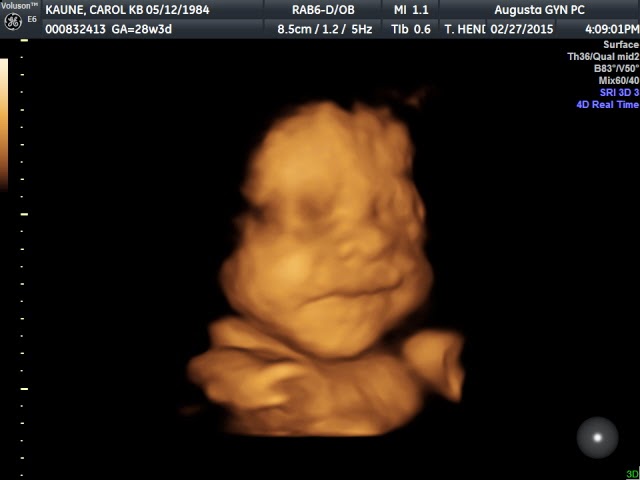

I think I am going to have to skip my 5 on Friday post this week because I will be in the midst of the consignment sale at Kennedy's daycare. However, I hope to be back next week with my 32 weeks post! My 32 weeks doctor's appointment is on Monday. Eeeek, can't believe it! So crazy that we will be meeting our son in such a short period of time.